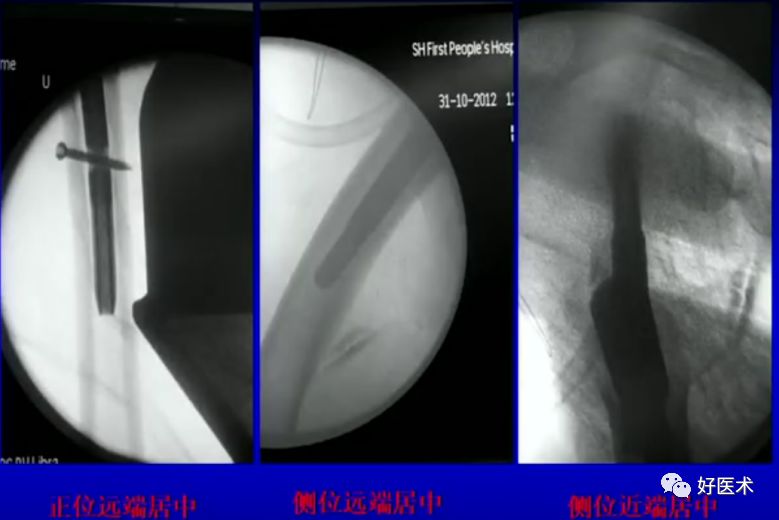

主钉插入后的导针正侧位

病例二:女 75岁

术前复位:

定位:

术后: